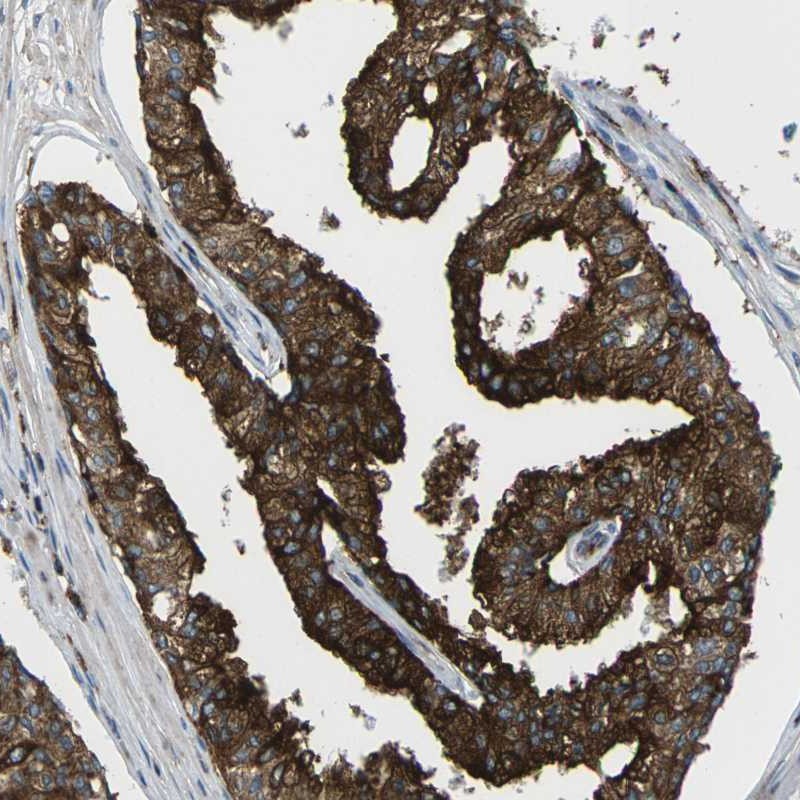

Immunohistochemical staining of human prostate shows strong cytoplasmic positivity in glandular cells.